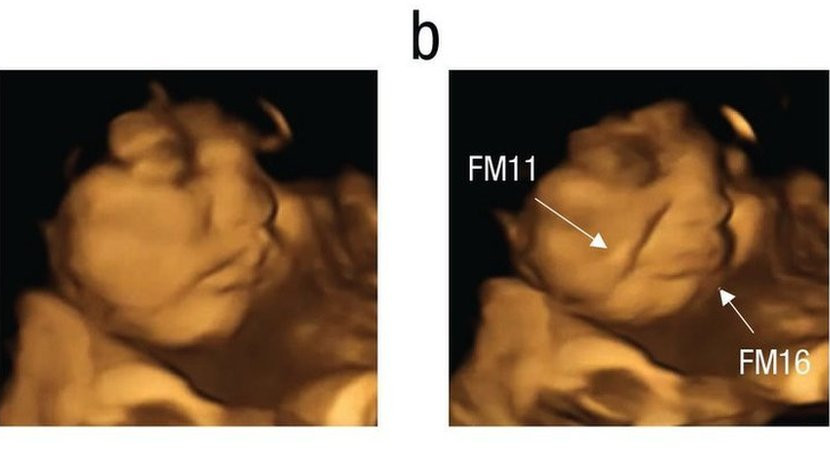

Fetal and Neonatal Research Lab, Durham UniversityReakcije ovog fetusa koji izgleda kao da se smeje, fotografisane su 20 minuta nakon što su majke konzumirale kapsule šargarepe u prahu Ukoliko vas ukus kelja tera da napravite grimasu, niste jedini. Naučnici su otkrili da se fetusi u materici smeškaju kada majke pojedu šargarepu i izgledaju kao da […]

U časopisu Psihološka nauka istraživači su objavili da su 20 minuta nakon što su majke progutale kapsule, 4D ultrazvučni pregledi pokazali da većina fetusa izloženih kelju izgleda kao da pravi grimasu.

Grimase i osmesi koji se vide na ultrazvuku „možda su samo pokreti mišića koji reaguju na gorak ukus“, kaže Rajsland.